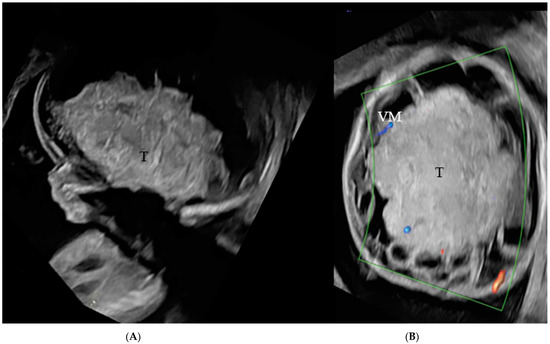

2. Case Series